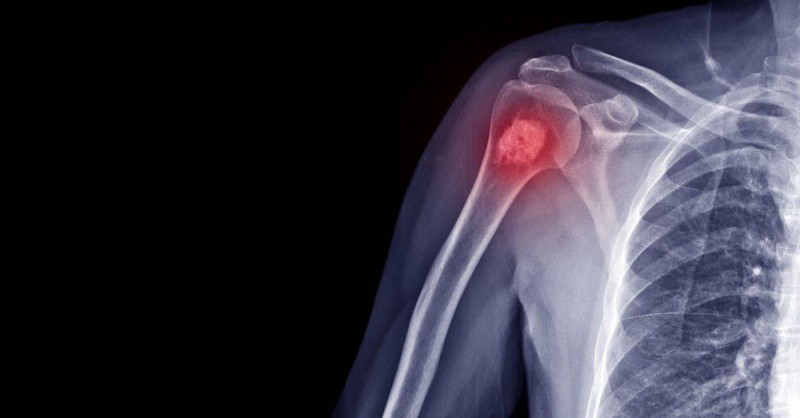

أفادت دراسة علمية حديثة بأن الناجين من السرطان البالغين، خصوصا أولئك الذين تم تشخيصهم في غضون 5 سنوات ولديهم تاريخ من العلاج الكيميائي، لديهم مخاطر متزايدة للتعرض لكسور العظام.

وذكرت الدراسة، التي أجراها باحثون في جمعية السرطان الأمريكية أن الناجين الذين كانوا نشيطين بدنيًا يميلون إلى تقليل خطر الإصابة بكسر العظام، أما الناجون الذين يدخنون كانوا مرتبطين بخطر أعلى.

وقالت الدكتورة إريكا ريس بونيا كبيرة العلماء في الجمعية: «هذه النتائج مهمة، من المتوقع أن يرتفع عدد الناجين من السرطان الذين يعيشون في أمريكا إلى 26.1 مليون بحلول عام 2040».